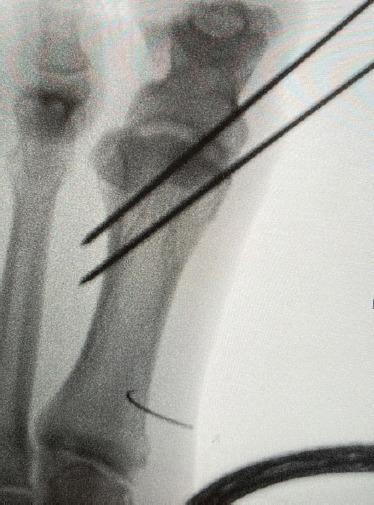

We present a case of spontaneous rupture of the extensor hallucis longus (EHL) tendon with significantly retracted tendon edges in a patient who had received multiple steroid injections to an arthritic talonavicular joint repaired using novel turndown flap technique.

This case details a patient who came in with a history of spontaneous EHL tendon rupture on a background of chronic pain in the midfoot due to osteoarthritis with osteophytes at the talonavicular joint for which they had received multiple steroid injections in the past. A novel repair technique was employed which involved split lengthening the proximal segment of the ruptured EHL tendon and making a turndown flap of the same by rotating the lengthened segment 180°, bridging the tendon gap. The lengthened tendon is then sutured to the distal segment of the EHL to achieve a tension-free repair. This bypasses any use of bridging allografts and autografts/tendon transfer, removing complications commonly associated with them.